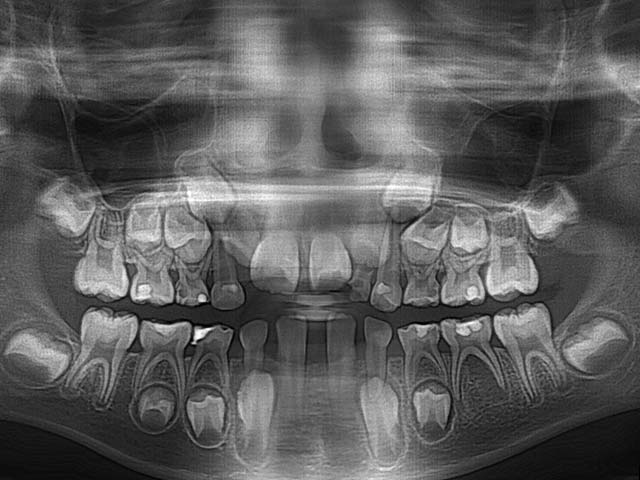

除此之外,兒童拍攝全口X光片還早期發現一些罕見疾病或先天缺牙如下:

1.左下先天性囊腫及缺牙

2.左下及正中門牙先天缺牙

3.右下先天缺牙第二大臼齒